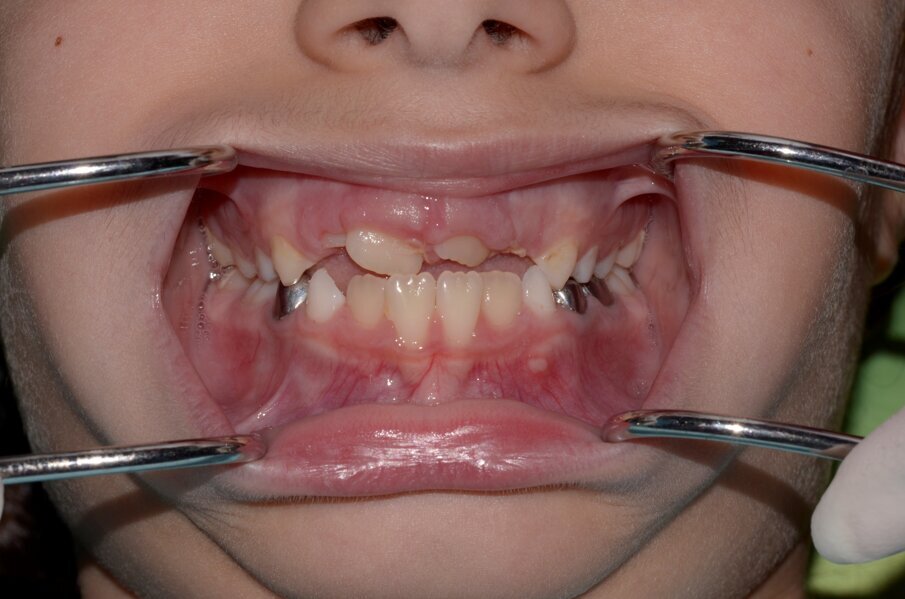

An eight and half year-old girl (LT) attended the paediatric dentistry department of Hamdan Bin Mohammed College of Dental Medicine (HBMCDM) in Dubai Healthcare City for an opinion. The patient’s mother was concerned about the delayed eruption of an upper front tooth (21) that was affecting her child’s appearance (Figs. 1 a, b & c). LT was medically fit and healthy with no history of previous dental trauma. She was in the mixed dentition stage. Tooth 11 had erupted 4 months ago in cross bite but 21 had not erupted yet. Its eruption was much delayed (usually erupts at 7 ½ years of age). Looking back at previous x-rays, a DPT was taken a year ago and it was noticed that an important feature was missed. Retrospectively, the presence of a supernumerary tooth ($) in the area of 21 and congenital missing 47 was confirmed (Fig. 2). Two new x-rays, namely upper intra oral periapicals and the parallax technique (distal shift) showed a supernumerary tooth (conical and inverted) in a palatal position (Figs. 3 a & b). LT also had dental caries of her primary teeth (Figs. 4 a & b), had a pronounced gag reflex and was dentally anxious.

Figs. 1 (a, b & c). An 8 ½ year old girl presented with delayed eruption of 21 and a palpable palatal swelling. Lower teeth were carious; see bitewings in Figure 4